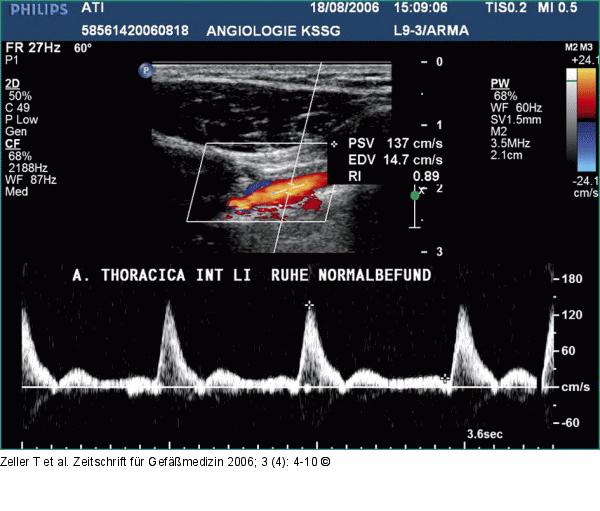

Abbildung 4: Arteria thoracica interna Triphasisches normales Dopplerprofil: Linke A. thoracica interna vor Bypassanastomosierung. |

Abbildung 4: Arteria thoracica interna

Triphasisches normales Dopplerprofil: Linke A. thoracica interna vor Bypassanastomosierung. |